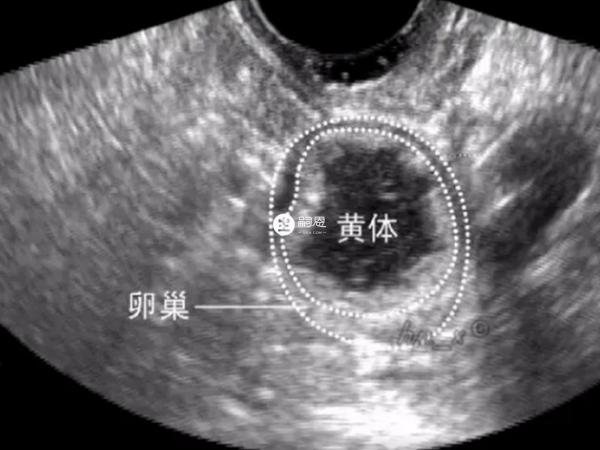

監測卵泡已經四次了,7月10日末次月經,7月18日有卵泡,大小為1.1*0.8,7月21日卵泡大小為1.2*1.0,7月24日長到了1.9*2.1,是個優勢卵泡,昨天再測,大夫說可能是之前那個排掉了,也可能是萎縮了。我昨天也有自己在家測排卵試紙,測到強陽,今天轉弱。請問如何確定是排了還是萎縮了?請問做陰超能準確的看出來嗎?做陰超是能夠準確的看出來優勢卵泡是萎縮了還是排出來了,因為B超監測卵泡發育是最簡單直接的方式,並且優勢卵泡萎縮後會在原來大小上變小並塌陷,而優勢卵泡排出陰超就會看到卵巢上沒有任何的無回聲區,也不會再看到有囊性暗區存在。所以說,優勢卵泡不管是萎縮還是排出都是可以通過超聲準確看出來的。

卵泡萎縮是指卵泡發育長大後沒有排出,卵泡就會逐漸變小或者是萎縮。而正常情況下,卵泡發育成熟會破裂排出卵子,稱為排卵。不管是優勢卵泡萎縮還是排出卵子都是可以通過陰超準確看出來的。下面就為大家介紹一下卵泡萎縮與排出的區別: